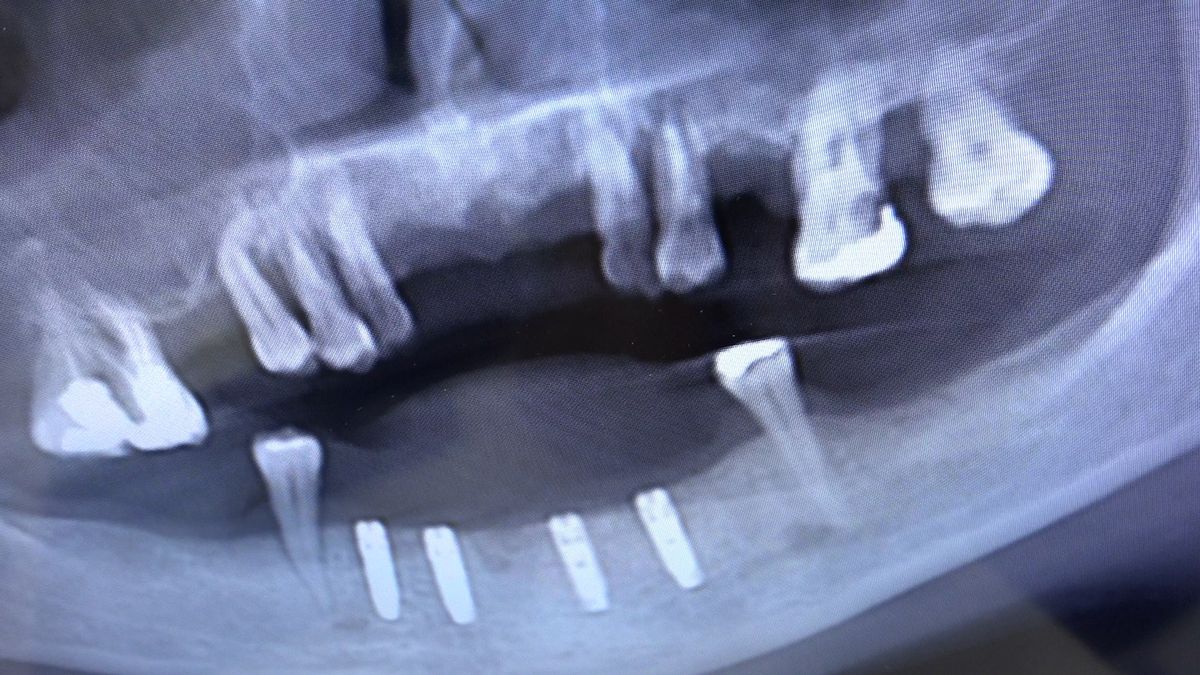

Tematem przewodnim 3 Sesji X Sezonu Practiculum Implantologii była protetyka na implantach. Lekarze przeprowadzili wiele procedur implantoprotetycznych pod kierunkiem dr n.med. Violetty Szycik, w tym oddanie prac przykręcanych i odsłonięcie implantów. Pod kierunkiem dr Małgorzaty Piotrowskiej wykonywali pobieranie wycisków z poziomu implantów tradycyjnie i za pomocą skanera. Zabiegi i ćwiczenia poprzedziły wykłady, które przeprowadził także technik dentystyczny Marek Wiligała.